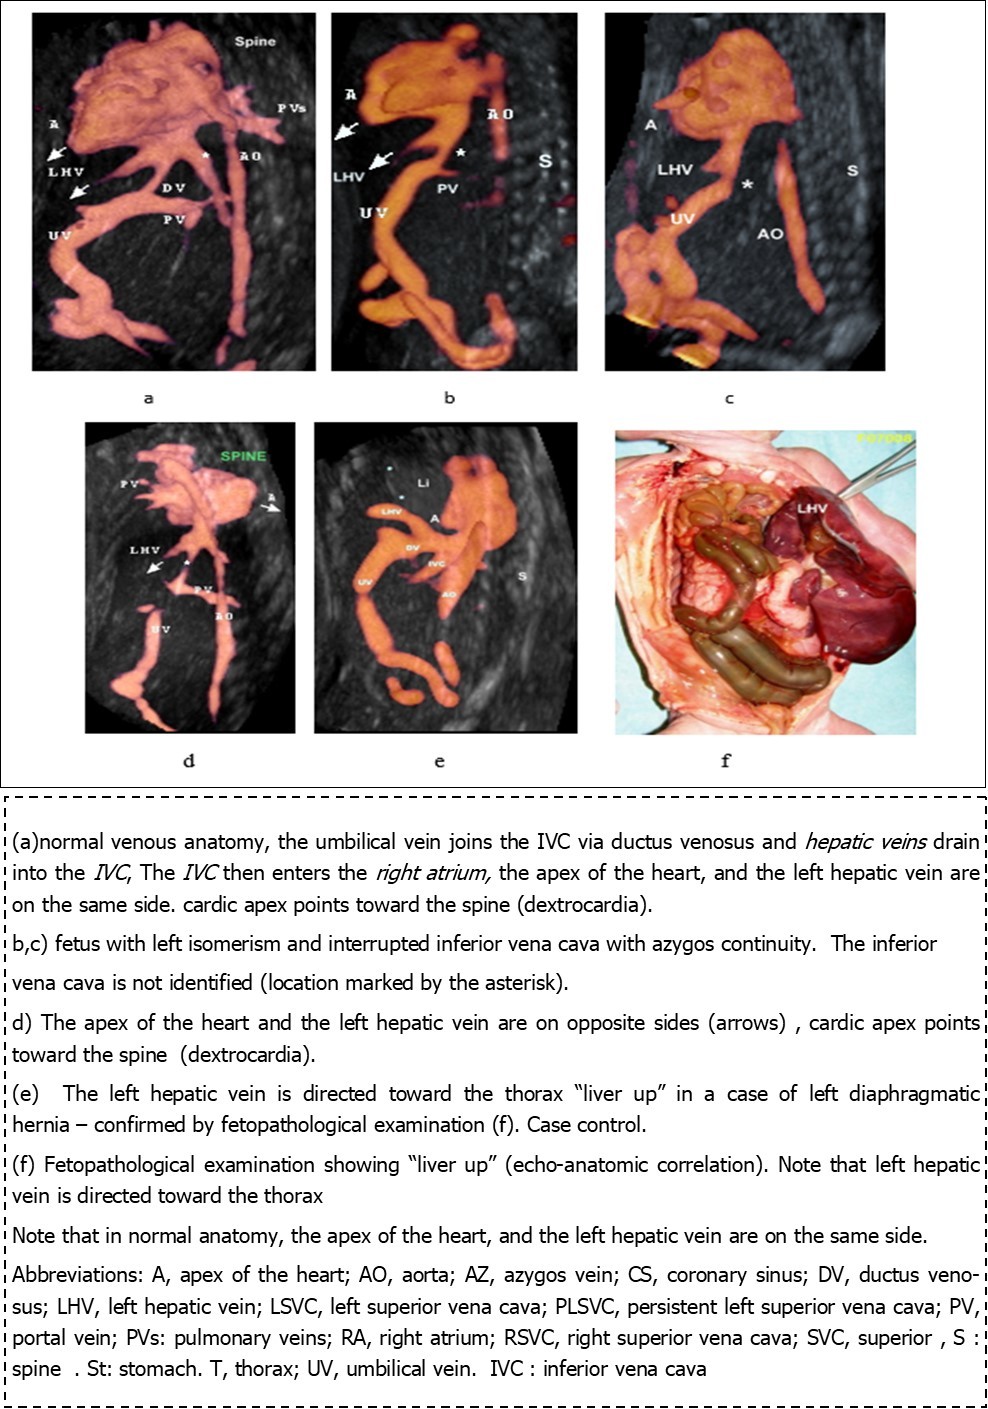

Figure 2.Three-dimensional ultrasound in glass body mode of a parasagittal view

One patient had dextrocardia in which the diagnosis was evoked by by Doppler imaging following localization of the apex of the heart and axis of the left hepatic vein on opposite sides, both left hepatic vein (LHV) and the apex of the heart are in the same side and point to the same direction i.e. downwards, the cardiac apex points to an opposite direction with respect to the spine i.e. away from the spine. (Figure 2d). In levocardia the cardiac apex is oriented away from the spine, on the other hand, in dextrocardia, the cardiac apex is oriented toward the spine (Figure 2). The 4 patients had a liver in the median position , one patient had the appendix appendix and gall bladder ((white asterisk) are on the left side, rectosigmoid is on the right side.(Figure 1 a,b,c,d,f). And another patient had intestinal nonrotation, the entire small bowel localizing to the right abdomen and colon localizing to the left abdomen. (figure g,h). One patient had congenital duodenal obstruction caused by Ladd's bands (Figure 1 I,j)

In our previous work 31, we demonstrated that, in parasagittal view, both left hepatic vein (LHV) and the apex of the heart are in the same side and point to the same direction. Thus , the diagnosis of dextrocardia is achieved by Doppler imaging following localization of the apex of the heart and axis of the left hepatic vein, furthermore, in normal position (levocardia) the cardiac apex is oriented away from the spine (Figure 2 a) , on the other hand, in dextrocardia, the cardiac apex is oriented toward the spine (Figure 2 d ) , to the best of our knowledge , this the first study evoking the diagnosis of situs using these parameters (orientation of cardiac apex with regard to LHV and spine). Another example demonstrating the utility of this parasagittal view is shown in (Figure 2 e, f), the LHV is pointing in the opposite direction to the cardiac apex i.e. upwards toward the thorax, a diagnostic clue to diaphragmatic hernia, in this case e diagnosis was confirmed by fetopathological examination. In addition, Grayscale facilitated the diagnosis of situs and confirmed the diagnosis of dextrocardia and right-sided stomach and midline position of the liver (Figure 1).

Any deviation from this standard anatomic position (cardiac apex and LHV are in the same side and point to the same direction i.e. downwards on the other hand cardiac apex points in an opposite direction from the spine), using either Galss body mode or power Doppler or Doppler angiography or greyscale would be necessities further evaluation. For example, (Figure 2 d) the cardiac apex and the LHV are in opposite directions and the cardiac apex points toward the spine, denoting an abnormal cardiac axis (Dextrocardia), thus using this parasagittal view, it is possible to diagnose this abnormality using either Doppler angiography with or without glass body mode.